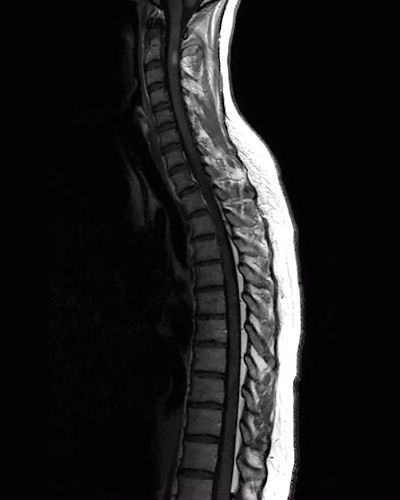

Mark the lesion in the scan